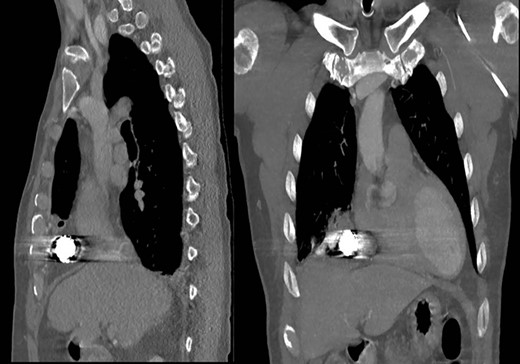

Representative coronal and sagittal images of the patient’s initial chest CT scan confirming the intrathoracic location of the foreign body with associated scatter due to its metallic contents.

A 59-year-old man was transferred acutely from another hospital for evaluation of a penetrating thoracic injury. The patient reportedly had been shot twice with a bean bag gun and sustained injuries to the right chest and flank during an altercation with police officers. The patient was breathing comfortably and normotensive, and his GCS was 15. He had a history of unprovoked pulmonary embolism and was taking apixaban. There was a 2-cm circular wound through the skin just superior to the right nipple and a 5-cm area of ecchymotic but intact skin over the right flank. A chest X-ray showed a 2-cm object with metallic density overlying the right thoracic cavity (Fig. 1). A chest CT showed the object in close proximity to the right atrium, right internal mammary artery and right middle lobe (Fig. 2). Additionally, a small amount of effusion consistent with hemothorax was present, for which a chest tube was placed. The patient was admitted for chest tube management and pain control, on the assumption that the metallic foreign body did not warrant operative removal.